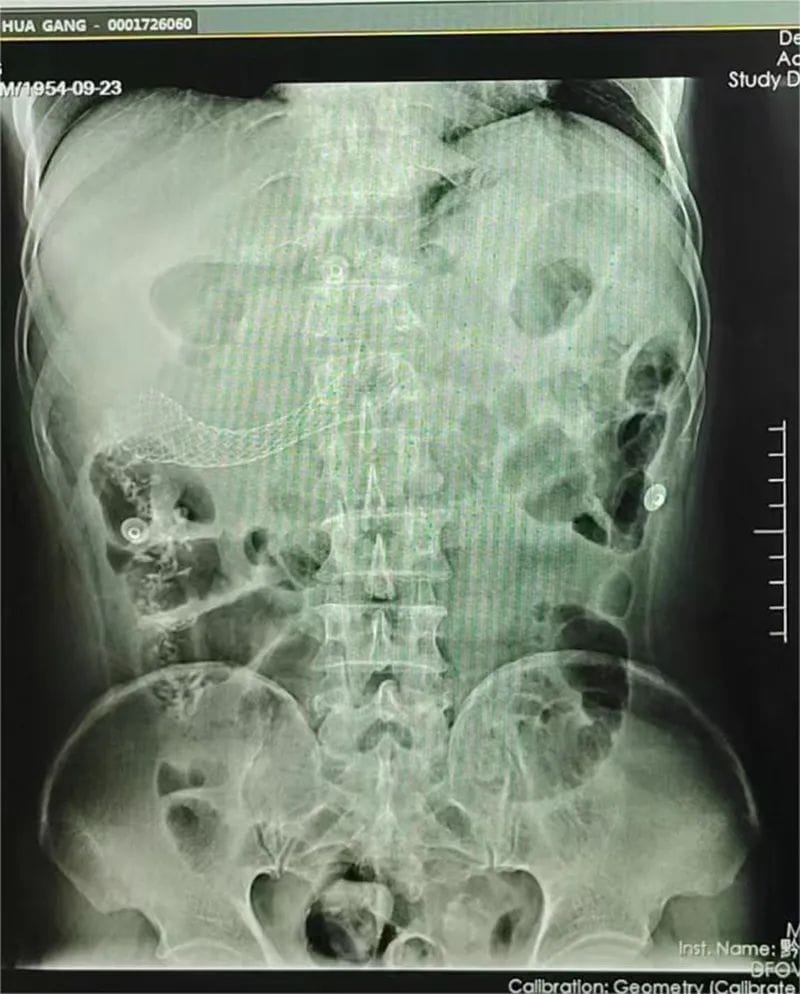

支架置入后

3月11日下午,邀请重庆医科大学第一附属医院文光旭教授作技术指导,在麻醉与围术期医学科和介入科的积极配合下,郭军博士带领团队利用C臂引导结肠造影为患者进行手术。医生在内镜下通过一根引导导丝将支架放到梗阻部位,并运用网状支架将肠道撑开,在堵塞的肠腔中撑开一条通道,形成真正意义上的“疏导”,为患者打通“生命通道”,手术顺利完成。